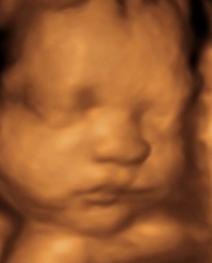

Innerview Ultrasound 3d Ultrasound Samples Philadelphia Pa